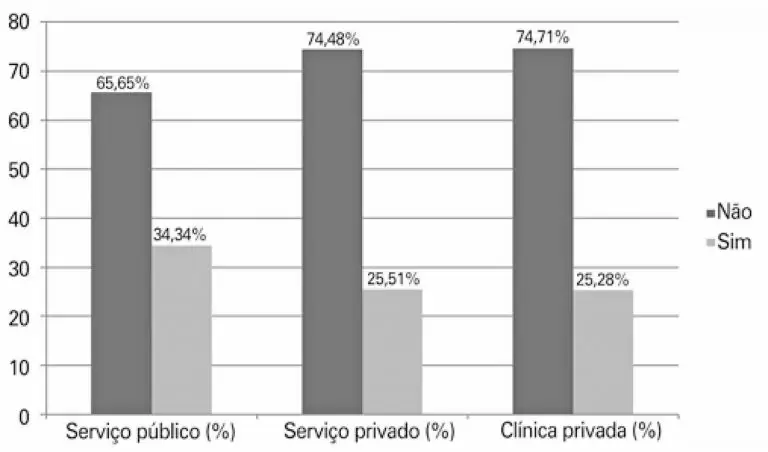

RESUMO Objetivo Identificar entre os cirurgiões pediátricos de todo o Brasil como é realizada a transição de cuidados dos pacientes pediátricos para as clínicas adultas. Métodos Um questionário foi enviado por e-mail para cirurgiões pediátricos cadastrados na Associação Brasileira de Cirurgia Pediátrica no ano de 2018. Foram avaliados dados como tempo de formação, idade máxima de atendimento, subespecialidade de atuação, seguimento ambulatorial de pacientes adultos, motivo pelo qual continuava atendendo pacientes adultos, encaminhamento para especialidades adultas, preocupação com a transição […]